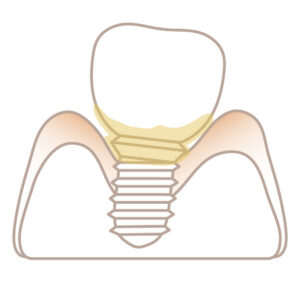

即時インプラント(最新のルートメンブレンテクニック)

歯周病とインプラントの怖い関係・・・